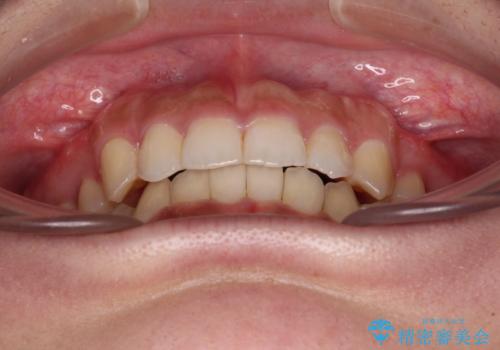

ワイヤー装置を用いた場合、一般的には2年程度で終了することを考えると、「移動量が多くなると治療期間が長くなる」というインビザライン矯正の最大の弱点が現れた治療となりました。

- 4年3ヶ月

- 治療費の目安: 100万円(税込)費用は治療当時の料金となります